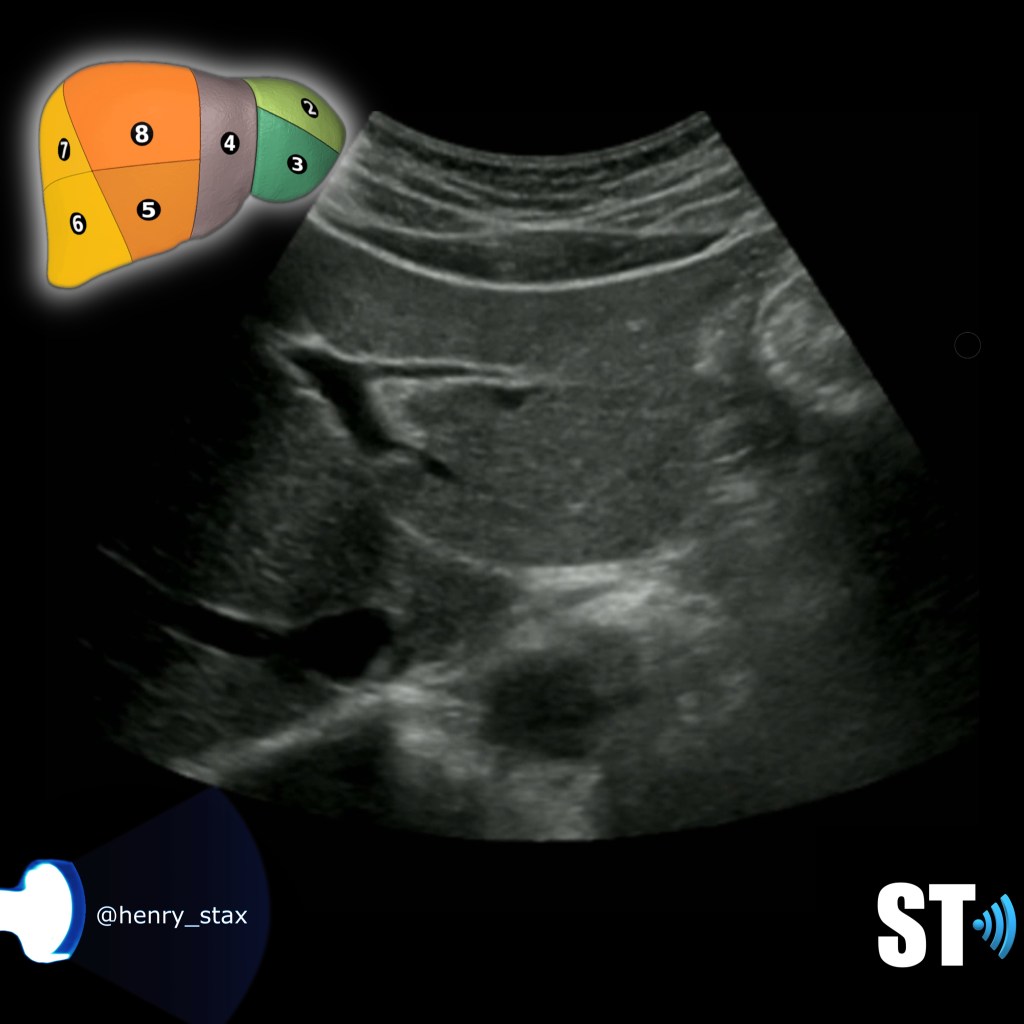

Transverse superior Rt lobe

Segments IVa VII, and VIII